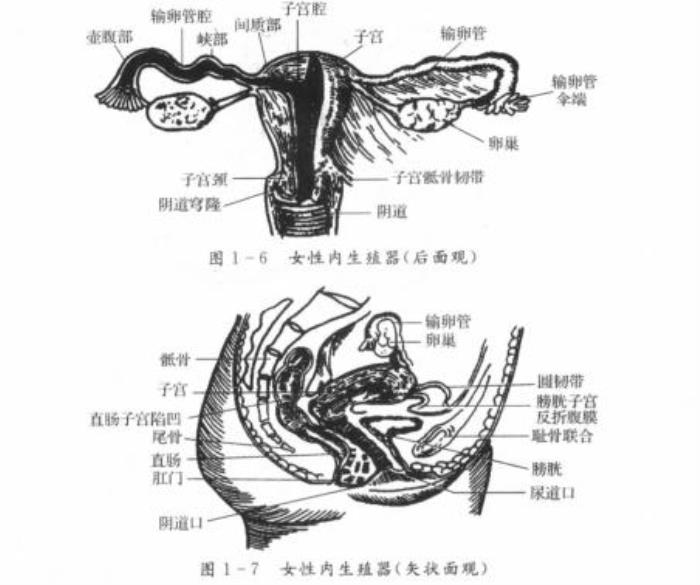

在产科及妇科超声检查中,主要有经腹部B超检查(下文简称腹超)和经阴道B超检查(下文简称阴超)两种方式,它们都可以有效帮助妇产科医生查明患者的盆腔、宫腔及附件区等部位的详细情况。

图1:妇科检查时B超检查的主要部位示意图。图源:邦彦医院学习资料

首先,医生会要求你憋尿,在膀胱充盈时,你才可以接受检查。从上图1我们知道膀胱在子宫的下方,做腹超前憋尿让膀胱充盈,可以使含有气体和内容物的肠道向四周推移,使超声束能以尿液充盈的膀胱作为透声窗,达到清晰显示子宫附件的目的。

阴超的探头是高频探头,扫射角度可达240度,当它被放入检查时(如下图),可以使检查声波更接近被检查的器官,因此能够更加清晰地探测子宫、卵巢的细小血流情况,更利于盆腔器官细小病变的诊断。比如辅助诊断子宫内膜增生、子宫肌瘤、卵巢肿瘤、阴道肿瘤、早期妊娠等妇科和产科常见症状。

图源:妇产科超声诊断